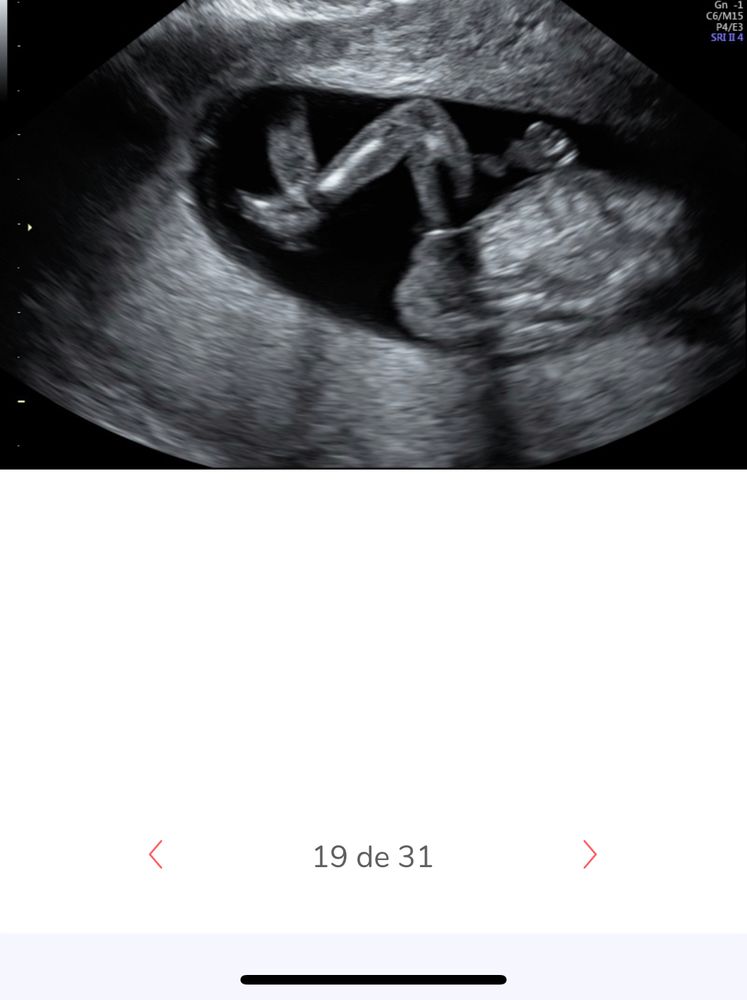

но вот на этом фото мне кажется то но бугорок ( слева обе ножки)